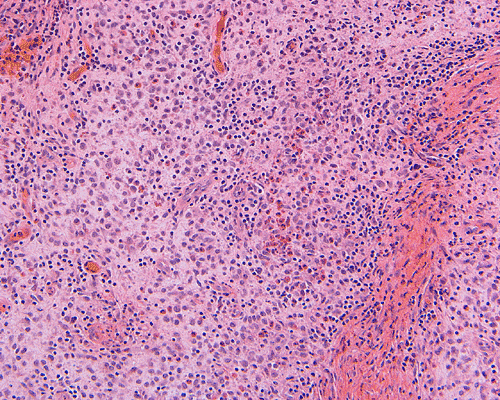

Clinical information: The patient was a 13 year-old girl who presented with worsening headache and some difficulties with memory, concentration and attention. MRI studies disclosed a 2.1 x 1.9 x 1.8 cm enhancing mass in the left temporal bone and sphenoid wing. The mass extended intracranially and abuts the left temporal bone accompanied by dural enhancement at that location. There is also extension through the bone into the submuscular temporal region. The following photos are taken from representative regions of the lesion. Panel 1 and 2 are CT scans at soft tissue and bone density respectively. Panel 3 and 4 are T1 weighed images without and with contrast respectively. Pandl 5 is proton density image. Panel A to D are cytologic (squash) prepartion for intra-operative consultation. Panel E and F are frozen sections for intraoperative consultation. Panel G to L are paraffin embedded sections.

Morphologic features are often sufficient to make an accurate diagnosis. Typical lesions are composed of medium sized to large Langerhans’ cells mixed with non-neopalstic inflammatory cells. The amount of eosinophils can vary from none 3 or scant to substantial. The Langerhans’ cells have only slight degree of atypia. Many of the nuclei have a characteristic deep groove parallel to the long axis, the so-called “coffee bean” nuclei. The amount of cytoplasm is usually moderate. Histiocytes (macrophages) are usually present and can be multinucleated. When histiocytes are present in large amount, they may make the diagnosis difficult. Similar to their non-neoplastic counterparts, tumor cells in Langerhans’ cell histiocytosis are positive for CD1a and S100 by immunohistochemistry. Histiocytes, on the other hands, are negative for S100 and CD1a 4, 5, 6 CD68 is helpful but not entirely specific in separating histiocytes from tumor cells in Langerhans’ cell histiocytosis. The proliferating fraction of can be recognized by immunohistochemistry for Ki67 (MIB-1) 6.